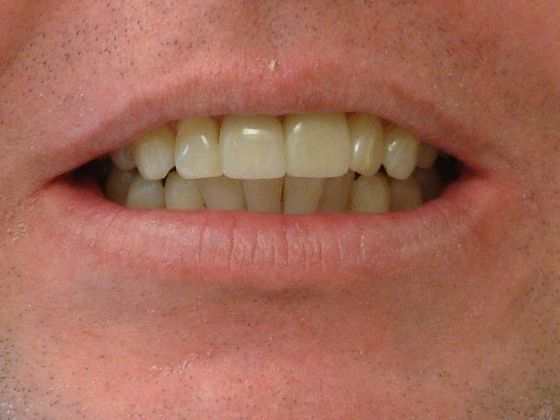

Jeffrey S. Kearney, DDS

Dr. Kearney specializes in comfortable, comprehensive dental services at his modern and inviting family practice in Cary, NC. He is trained to surgically place and restore dental implants and also offers the latest treatments to treat TMJ issues, sleep apnea, and orthodontic problems. Prestigious affiliations include: